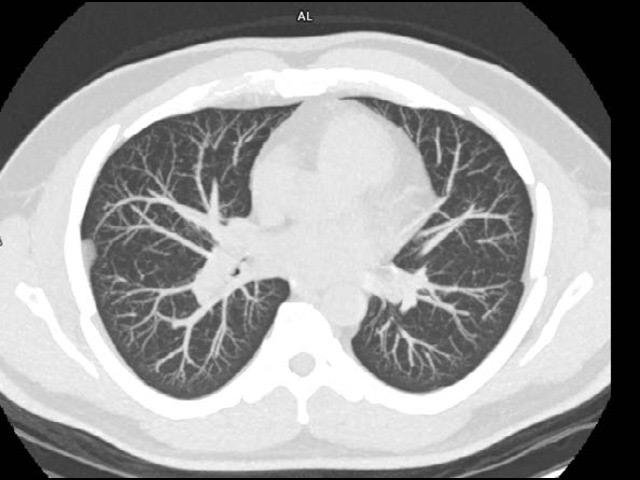

With a mobile lung cancer screening program, you can bring the low-dose CT exam that at-risk patients need closer to where they live. With a short set-up, our self-contained Mobile Lung Screening Solution with a SOMATOM go.Up CT scanner offers the high image quality, ease of use, and flexibility you need to create a lung screening program that meets the real-life needs of your community.